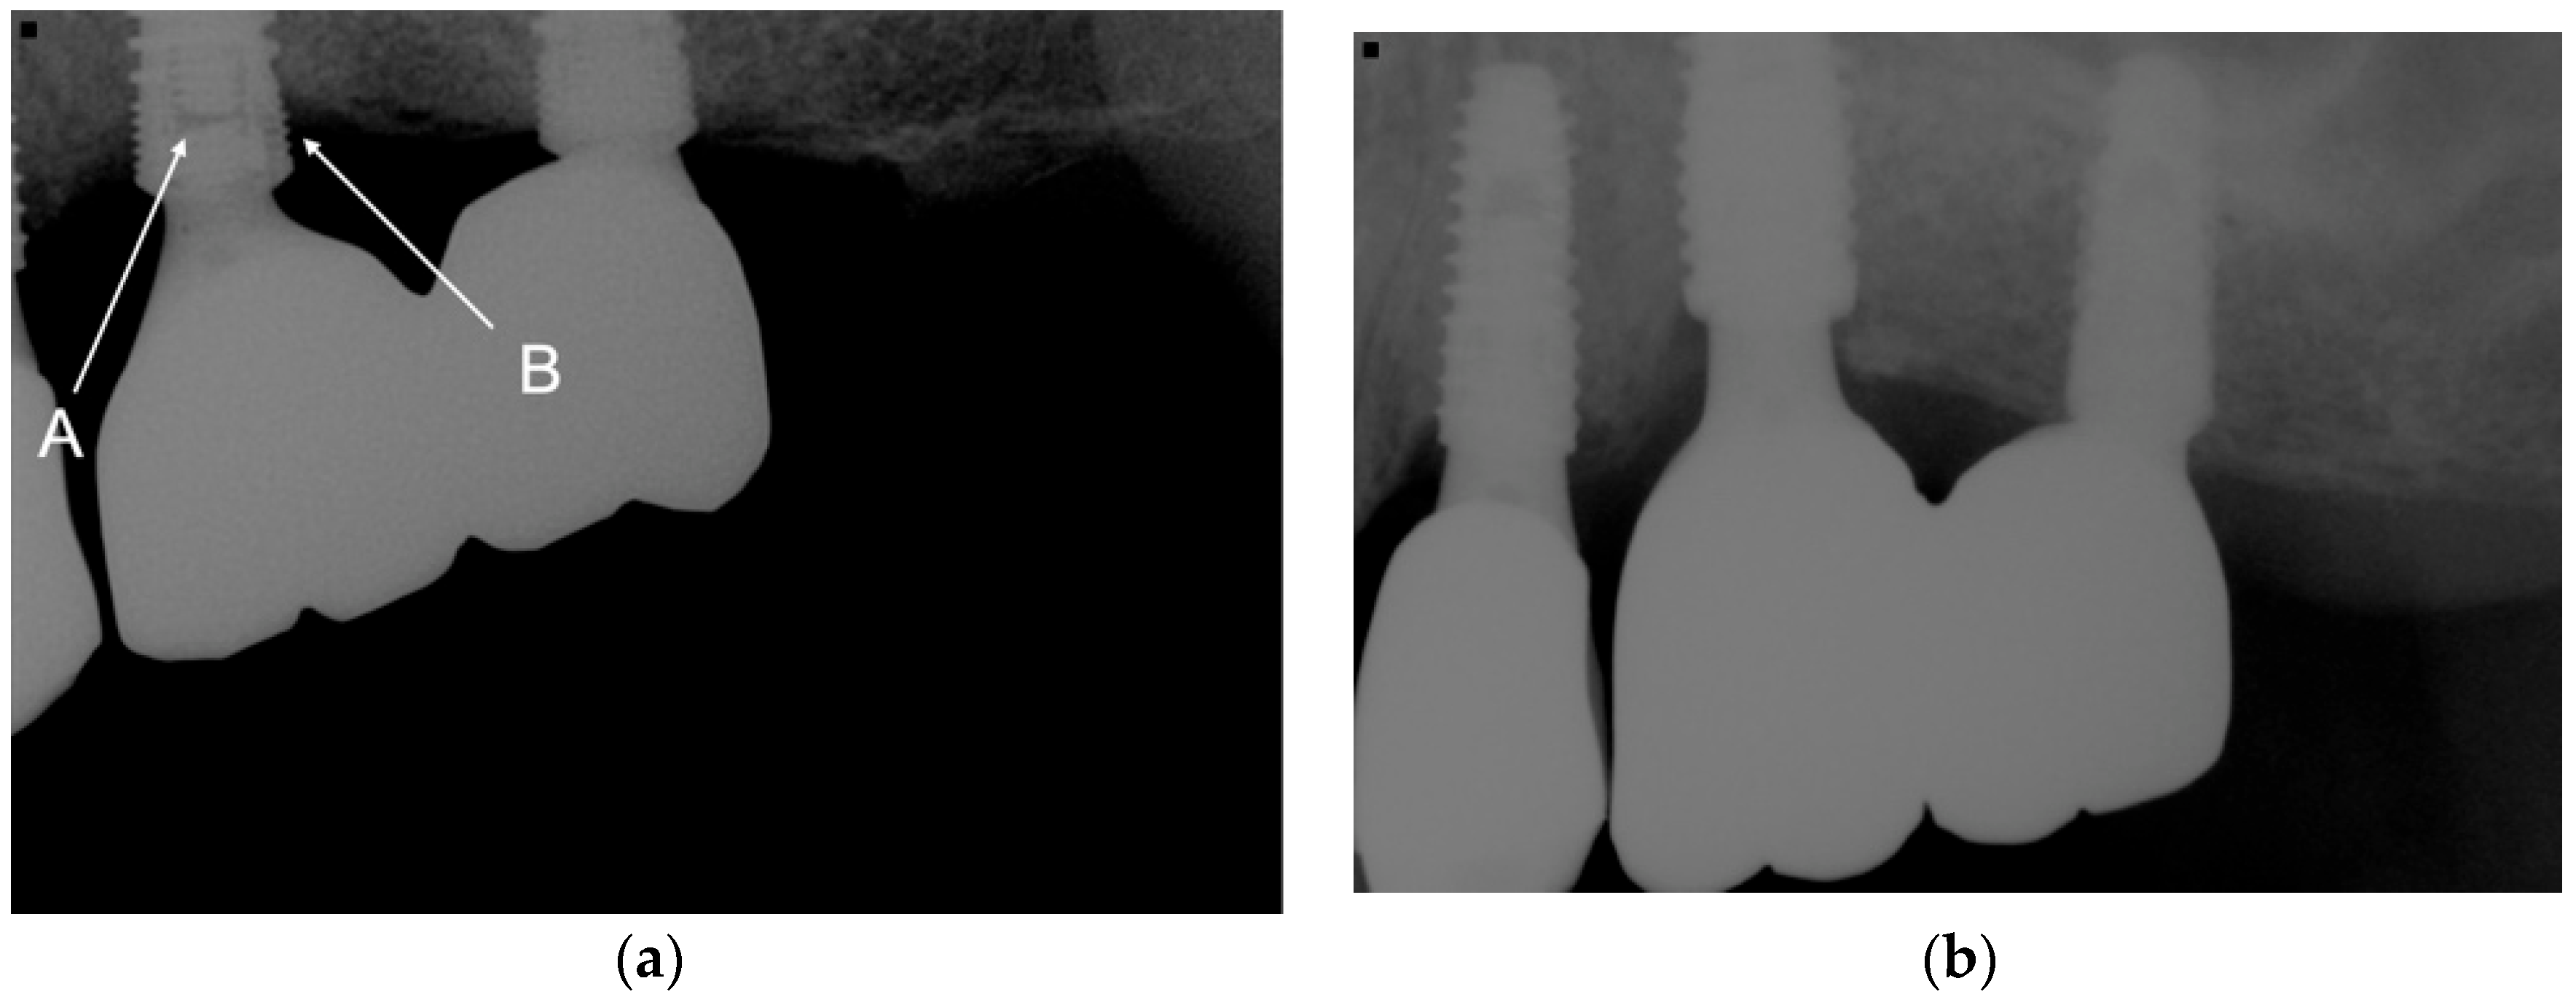

3.3. Bone Level Comparison